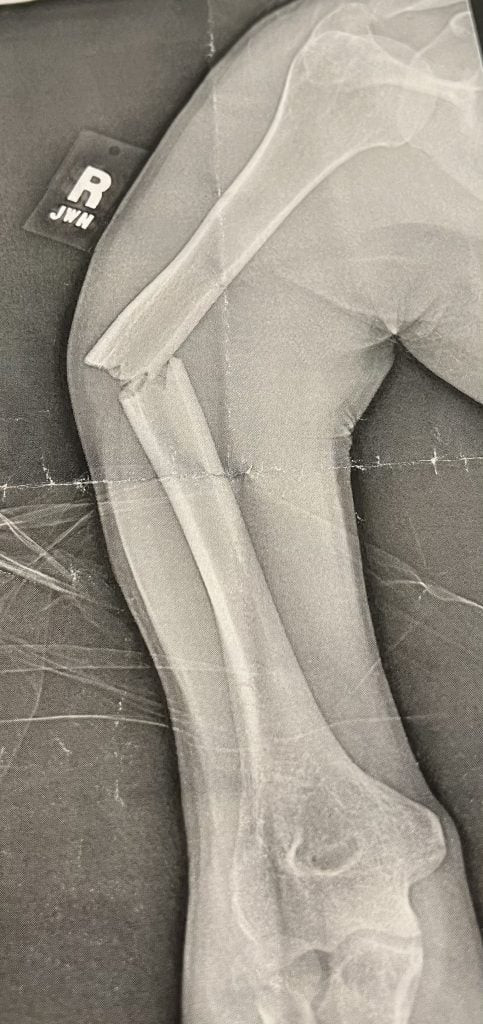

I broke my arm on August 11, 2022 after having a traumatic fall off my horse. I live in Charlotte, NC. After trying to heal naturally for 3 months I was frustrated with my doctor as he couldn’t tell me why I wasn’t able to heal. I then found out about HSS and found Dr. Sama. I had a virtual appointment with him in November 2022. He spent almost an hour on the virtual call with me and my husband. After that appointment I knew that I would have no one but Dr. Sama operate on me. On January 5th he performed an open reduction internal fixation on the transverse fracture of my humerus in my dominant right arm. Today, May 3rd, almost 4 months later I had my final follow up with him. He said that my fracture is officially healed! I’ve been working hard every single day to get both mobility and strength back in my arm. I’m back doing all the activities I love! I cannot thank Dr. Sama enough for everything. He is the BEST!